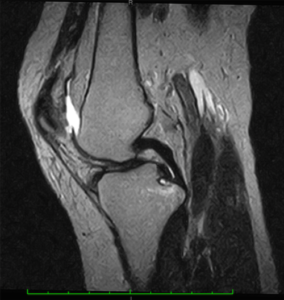

PCLは膝屈曲60度にて最大伸張を示し、膝屈曲0度及び120度で弛緩することが報告されています。

そのため、膝伸展位では関節に動揺は起こらず、階段を上り下りするときなどに膝屈曲60度前後で力を入れると不安定感を訴えます。

PCLを切離した場合は、脛骨の後方移動距離が膝関節60〜90度屈曲位で約3倍になるとされています。